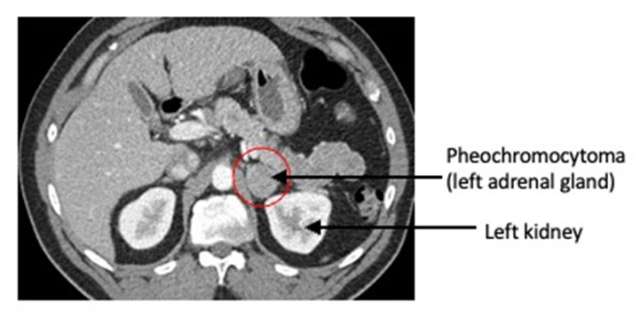

Pheochromocytoma, left adrenal gland >

Anyone with an adrenal nodule discovered on imaging (e.g. a CT scan or MRI of the abdomen) should have appropriate biochemical work-up to determine if the adrenal nodule is producing excessive hormones. This is done by laboratory testing of the blood and/or urine. Pheochromocytomas have specific imaging characteristics that can be evaluated on CT or MRI.

CT or MRI of the abdomen will almost always identify a pheochromocytoma. Additional specialized imaging such as MIBG (meta-iodobenzylguanidine) or Ga-68 Dotatate PET/CT scan can help to confirm a pheochromocytoma and identify multiple tumors or metastatic spread.